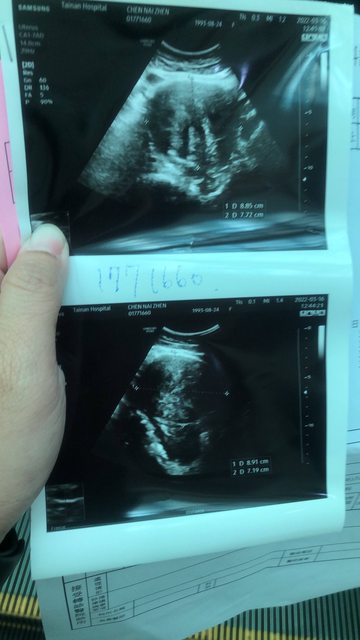

3/16到部立醫院看診後,蔡永隆醫生看到轉診單立即安排照超音波,照超音波時告知肌瘤已經大到9公分(我子宮原始內徑為7公分),是需要開刀的尺寸。

https://i.imgur.com/pedJOLN.jpg